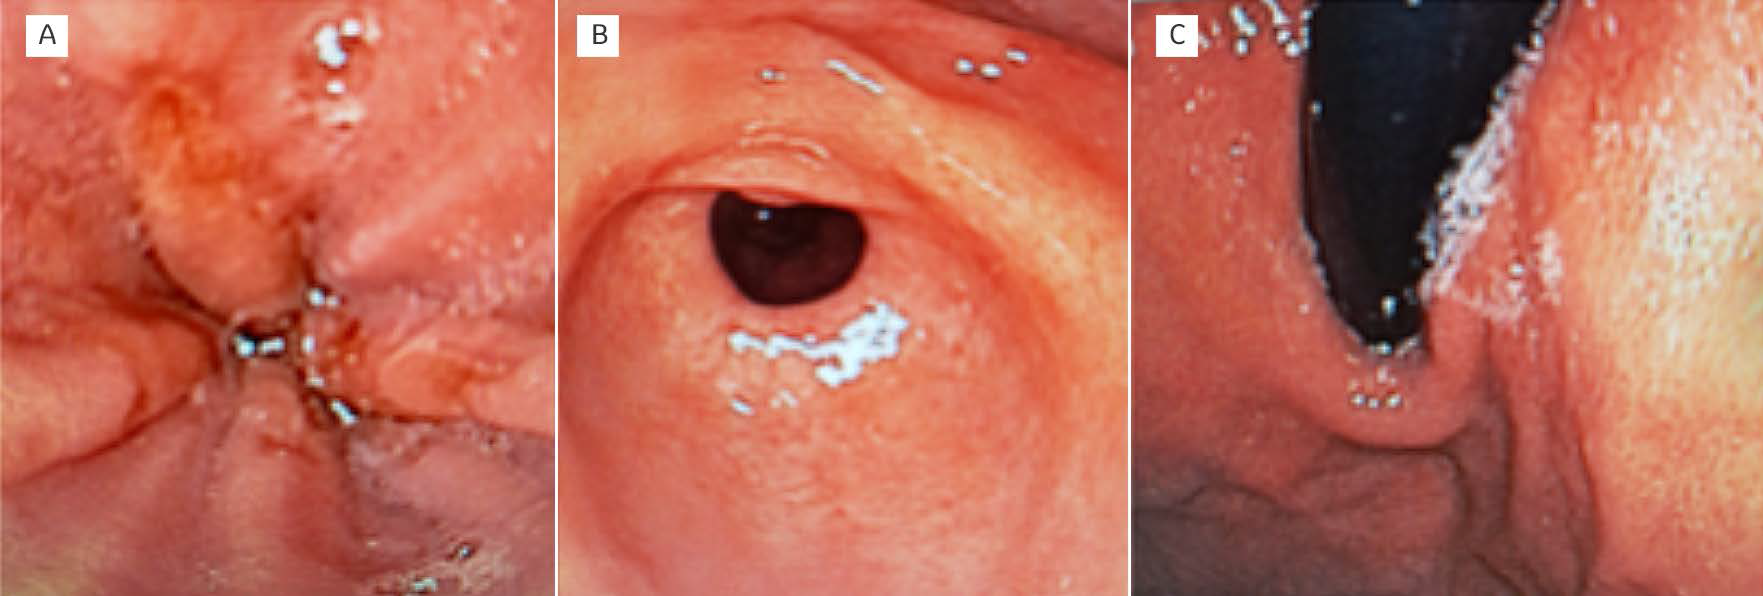

Inicialmente, se realizó abordaje para sangrado de tubo digestivo alto con ultrasonido abdominal en búsqueda de alteraciones anatómicas, el cual se reportó normal. Posteriormente, bajo anestesia general se realizó panendoscopia encontrando gastropatía erosiva hemorrágica y duodenitis hemorrágica sin sangrado activo (Figura 1). No se encontraron macrófagos cargados de hemosiderina (siderófagos).

Figura 1 Imágenes de endoscopia gastrointestinal. A) Erosiones esofágicas sin sangrado activo. B) gastritis superficial con puntilleo hemorrágico en antro y región prepilórica, sin sangrado activo. C) fondo gástrico de aspecto normal. Hiato competente.